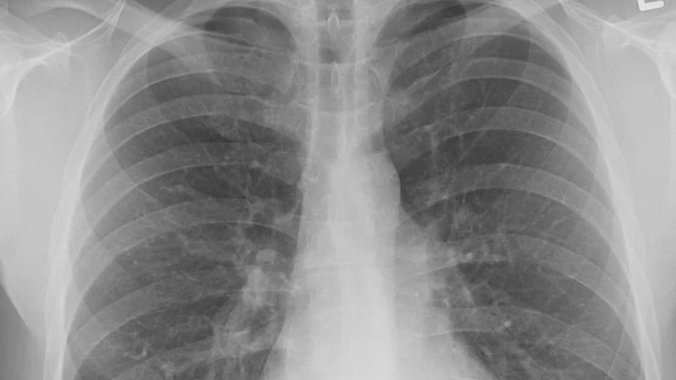

- Ukoliko posumnjamo na rak pluća obavezno se uradi rengentski snimak pluća, na kome postoje promene u vidu tzv. zasenčenja. Svaki kašalj koji traje duže od dve nedelje potrebno je dopuniti snimkom pluća. Skener pluća (CT pluća) može dati informacije o veličini, položaju tumora pluća i odnosu tumora sa drugim organima. Uobičajeno se da se ovaj snimak radi sa kontrastom, a važan je podatak da li postoje uvećane limfne žlezde. To sve pomaže da se proceni proširenost bolesti tj. stadijum bolesti. Kod sumnje na postojanje metastaza rade se i skenerski pregled glave i trbuha - objašnjava doktorka Radosavljević.

Foto: Unsplash.com/Pink,rs